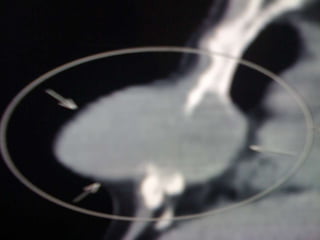

• USG ABDOMEN- HETEROECHOIC LESION

RIGHT LOBE OF LIVER-11.5×10.5 CM –

• IMPRESSION- HCC Rt. LOBE OF LIVER

INVESTIGATIONS • CBC- NORMAL •LFT- S. BILIRUBIN- 1.3 DIRECT- 0.9 ALK.POS- 80 T.PROT- 6.8 ALB- 3.7 • RFT- NORMAL • HbSAG- NEGATIVE • ANTI HCV- NEGATIVE • HIV I & II- NEGATIVE • ALPHA-FETO PROTEIN- 1.62 IU/ml • USG ABDOMEN- HETEROECHOIC LESION RIGHT LOBE OF LIVER-11.5×10.5 CM – • IMPRESSION- HCC Rt. LOBE OF LIVER